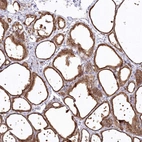

Immunohistochemical staining of human thyroid gland shows strong cytoplasmic positivity in glandular cells.